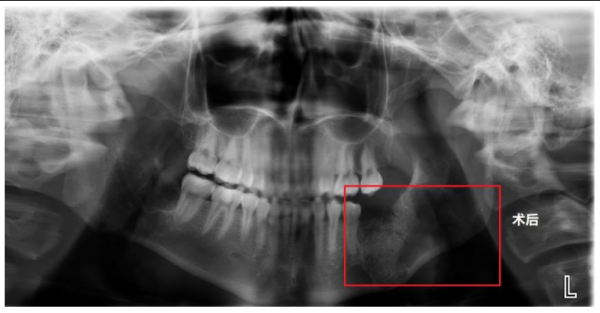

在经过充分的术前准备后,贺祖武带领团队利用超声骨刀精准去骨,最大程度减少患者的术区创伤,保留足够的颌骨骨量,尽量避免下颌骨出现病理性骨折。术中,还同期应用浓缩生长因子(CGF)凝胶混合骨填充材料,植入术区的创口,促进骨组织再生及愈合,确保术后功能与美观兼顾,极大限度减少对患者生活质量的影响。手术历时1小时顺利完成,患者术后恢复良好,次日即可进食流质饮食。术后X片显示,其被囊肿侵蚀的颌骨缺损区已成功植入人工骨材料,为后续种植牙打下基础。

术后X片显示,被囊肿侵蚀的颌骨缺损区已成功植入人工骨材料